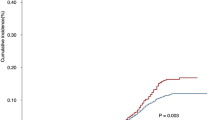

The dose differences of the four DEs were listed in Table 2. Compared with the SD-IMRT plan, different DEs resulted in similar dose increase in the SIB-IMRT plan. The increase of V30, V40 and V50 for the four DEs was comparable (p > 0.05). However, the increase of V60 and Dmean was significantly different (p < 0.05). Specifically, V60 values for the ESOwhole, ESOinfield, ESOinfield-tumor and ESOwhole-tumor were increased by 29.6 cc, 29.5 cc, 3.4 cc and 3.7 cc, respectively. Dmean for ESOwhole, ESOinfield, ESOinfield-tumor and ESOwhole-tumor were increased by 7.2 Gy, 10.9 Gy, 4.6 Gy and 2.0 Gy, respectively. However, Dmax values for the ESOwhole, ESOinfield, ESOinfield-tumor and ESOwhole-tumor were equally increased by 14.2 Gy. Compared with ESOwhole-tumor and ESOinfield-tumor, the increase of V60 and Dmean was higher for the ESOwhole and ESOinfield definitions. The dose volume histogram (DVH) for the four DEs was presented in Fig. 1. The dose variation for the four DEs in the sagittal view from one representative case was illustrated in Fig. 2.

DVH for different DEs. (A) DVH for ESOwhole, (B) DVH for ESOinfield, (C) DVH for ESOinfield-tumor and (D) DVH for ESOwhole-tumor. ESOwhole = the entire esophagus including the tumor; ESOinfield = the portion of ESOwhole within the treatment field; ESOinfield-tumor = the portion of ESOinfield, excluding the tumor; ESOwhole-tumor = the portion of ESOwhole, excluding the tumor. SIB-IMRT = intensity-modulated radiation therapy with simultaneous integrated boost; SD-IMRT = standard-dose intensity-modulated radiation therapy.